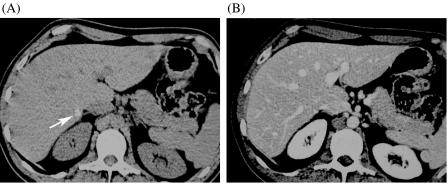

In contrast to other extrahepatic malignancies many colorectal cancers can be cured even when there is metastatic spread to the liver. The diagnosis of liver metastases relies totally on imaging to decide which patients may be surgical candidates. The diagnostic value of ultrasound with contrast agents, multidetector CT and MR imaging with non-specific gadolinium chelates and liver-specific contrast agent is discussed. Nowadays MDCT is the mainstay of staging and follow-up of these patients, because it provides good coverage of the liver and the complete abdomen and the chest in one session. MR imaging has been shown to be superior to helical CT in the preoperative assessment of colorectal liver metastases. Large studies are needed to define the role of MDCT vs. MRI staging in patients referred for resection of liver metastases.

与其他肝外恶性肿瘤不同,许多结直肠癌即使已发生肝转移仍可治愈。肝转移的诊断完全依赖影像学检查来确定哪些患者可能适合手术。本文讨论了超声造影、多排CT以及使用非特异性钆螯合物和肝脏特异性造影剂的磁共振成像的诊断价值。目前,多排CT是这些患者分期和随访的主要手段,因为它能在一次检查中对肝脏、整个腹部和胸部进行良好的覆盖。在结直肠癌肝转移的术前评估中,磁共振成像已被证明优于螺旋CT。需要开展大型研究来明确多排CT与磁共振成像在肝转移瘤切除患者分期中的作用。